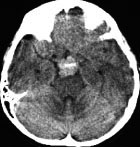

全脳照射後の脳内石灰化(幼児例)

20年以上前のことですが,髄芽腫の1歳6ヶ月の子どもに25グレイの全脳照射をしました。これは15年後のCTです。

脳の萎縮は目立ちません。認知機能は低いのですが支援を受けて学校へ行けています。下垂体機能は低下して成長ホルモンなどの補充をして普通に暮らせています。

CTで,両側の大脳基底核(被殻と淡蒼球)と視床後部に石灰化がみられます。乳幼児期に放射線治療を受けた子どもに見られるものです。